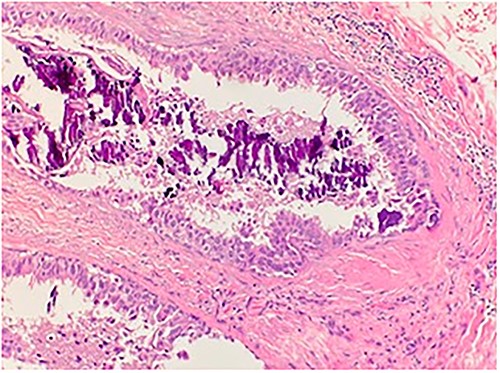

An 84-year-old female presented to the breast surgery office for biopsy proven malignant 2-cm palpable mass on physical examination in the right retroareolar region. Her medical history was significant for hypertension, diabetes mellitus, and stroke. She had a diagnostic bilateral mammogram and sonogram along with a biopsy of the site in question, at another outside facility, which had yielded invasive ductal carcinoma with perineural invasion. In addition, indeterminate linear microcalcifications were visualized in the central right breast 3-cm posterior to the mass and also in the central far posterior lower right breast. These warranted another diagnostic mammogram and sonogram. Repeat diagnostic mammogram and sonogram were remarkable for: biopsy-proven malignant 1.2-cm mass in the right retroareolar region. Additional suspicious microcalcifications 3- and 7-cm posterior to the mass were noted, classified as BIRADS 4. She underwent a stereotactic biopsy. Pathology for the retroareolar mass was positive for moderately differentiated invasive ductal carcinoma with perineural invasion and pathology for calcifications was positive for Ductal Carcinoma in Situ (Fig. 1). Invasive ductal carcinoma was positive for ER (95%), PR (50%), and negative for Her-2/Neu. Ductal Carcinoma In Situ was positive for ER (90%–95%) and negative for PR (0%). Subsequently, upon an extensive discussion with the various options including but not limited to lumpectomy and mastectomy, she elected to undergo a right simple mastectomy without reconstruction with right axillary sentinel node biopsy. Surgical pathology was remarkable for no evidence of active malignancy in any of the previously biopsied areas; evidence of nodular necrosis of tumor cells noted (Fig. 2) consistent with inflammatory reaction and fibrocystic changes. Patient was started on Anastrozole and the following postoperative course was unremarkable.

Microscopic examination shows a sheet of nonviable tumor cells with necrosis. H&E 20×.